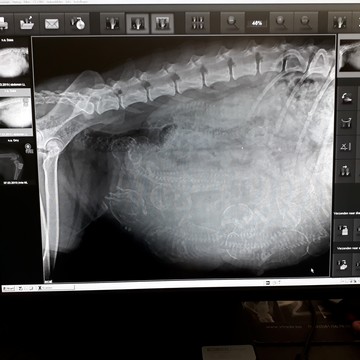

7 maart 2019

Does doet haar Portugese afkomst eer aan: ze krijgt een groot gezin. De röntgenfoto die vandaag is gemaakt wijst uit dat ze geen 4 puppy's verwacht, maar waarschijnlijk een nestje van 10 puppy's krijgt! Volgende week is Does uitgerekend. Het gaat heel goed met haar en ze wordt steeds dikker. Ze eet prima, zij het verdeeld in kleine porties over de dag. Het wordt voor haar en voor ons een spannende week.